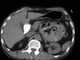

Paraduodenal hernia

Internal hernias occur when there is protrusion of an internal organ into a retroperitoneal fossa or a foramen (congenital or acquired) in the abdominal cavity. If a loop of bowel passes through the mesenteric defect, that loop is at risk for incarceration, strangulation, or for becoming the lead point of a small bowel obstruction. [Source: Wikipedia ]